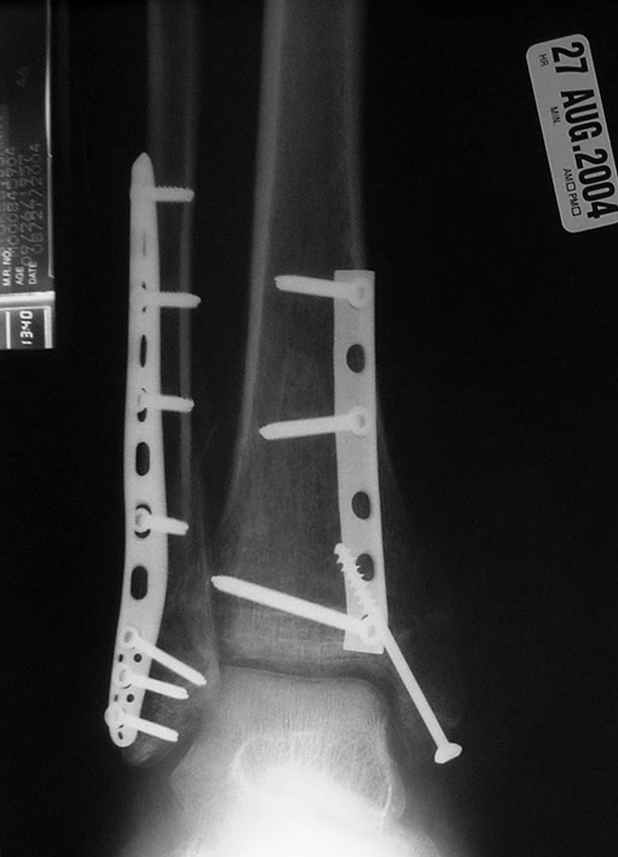

Второй случай сделан из одного разреза

Дж